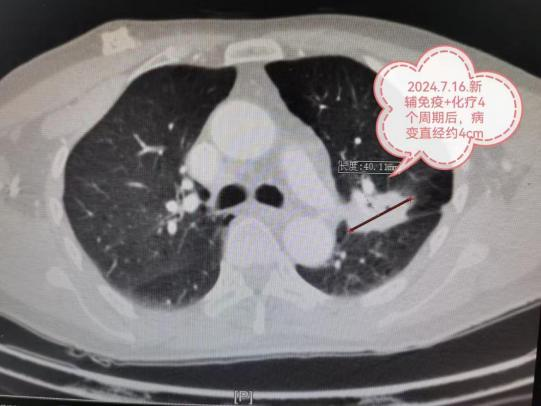

(三)新辅助治疗后的肺癌微创根治术

偏晚期的肺癌手术机会渺茫,新辅助治疗(术前免疫、靶向、化疗等)可让患者重获根治性手术机会。如图:7.7cm左上肺癌,若直接手术,可能无法切除或被迫切除左全肺。新辅助免疫+化疗4个疗程后,病变由7.7cm缩小到4cm,在单孔胸腔镜下肺动脉成形完成左上肺癌根治术(左上肺叶切除+淋巴结清扫),不仅只切除了左上肺保留住了左下肺,而且术后病理检查显示术前用药后残存癌细胞比例仅残存6%,也就是说4cm肿块里面94%的组织已经没有癌细胞,远期疗效更佳。